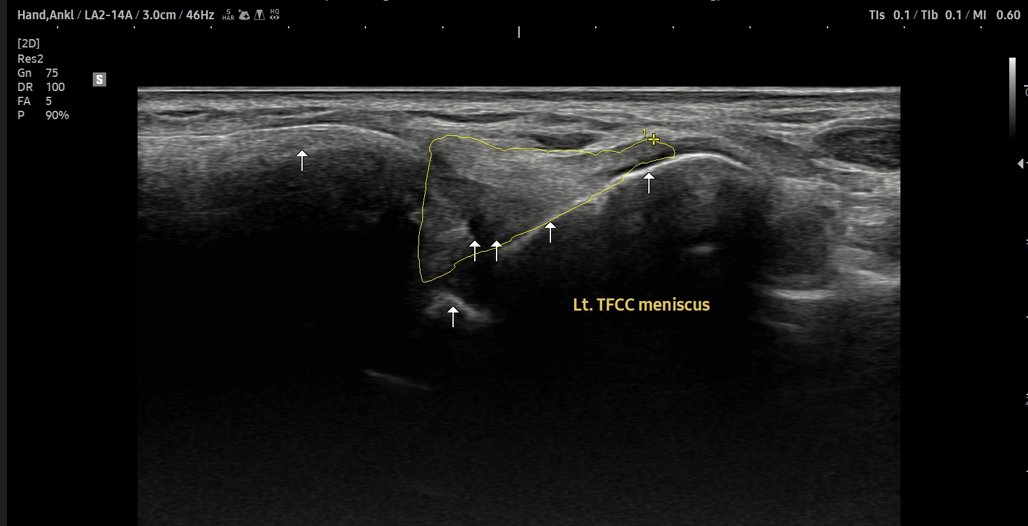

- 치료기간 : 25 . 8 .19 ~ 25 . 11 . 20

- 치료횟수 : 25 회 (사이클 치료 3 +아피톡신 10회)

치료 전

치료 후

좌측 골프엘보 : 12/2

좌측테니스엘보: 12/8

우측 골프엘보 : 12/2

우측 테니스엘보: 12/8